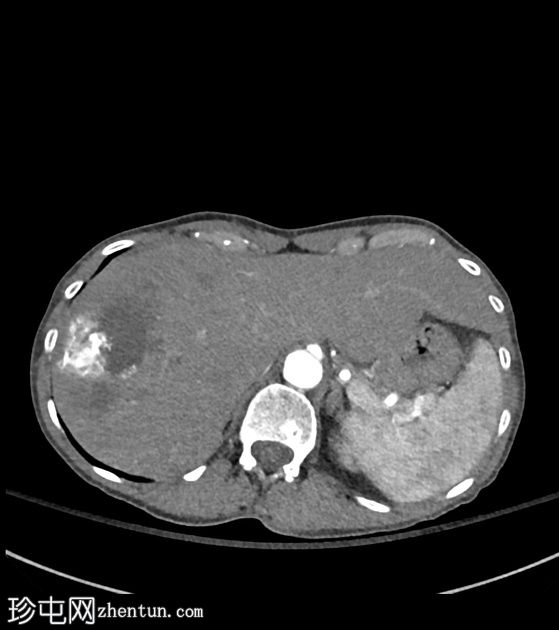

CT扫描

轴向

非造影

肝段VIII区中心可见一囊性坏死灶,边缘不规则,周围可见粗钙化,造影后无明显强化。轻度包膜回缩及邻近灌注改变。肝穹窿内可见其他较小的卫星囊性灶和多处粗钙化。肝门部可见浸润性组织,部分钙化,导致门静脉轻度狭窄和右侧肝内胆管轻度扩张。

CT表现符合肝泡包虫病。